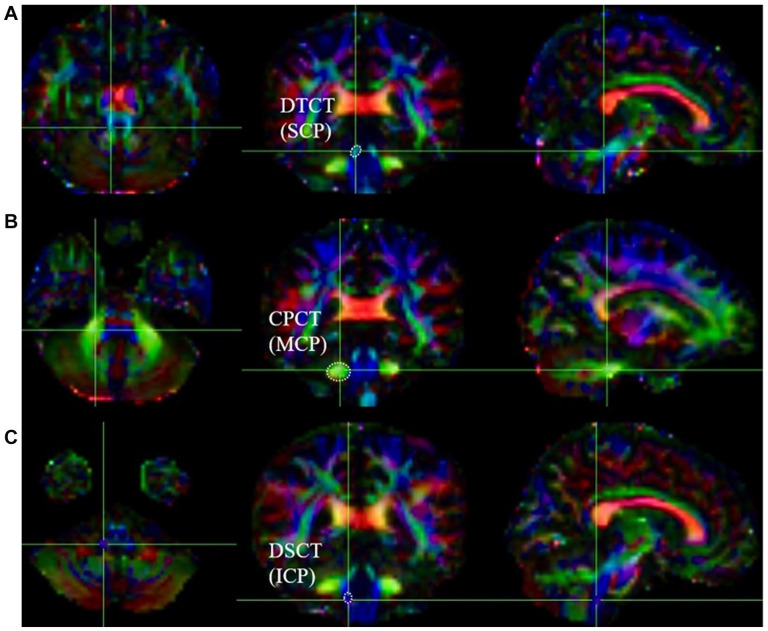

BackgroundThe cerebellar cortex has gradually become a promising therapeutic target for improving motor recovery post-cerebral infarction, potentially dependent on the structural integrity of motor-related corticocerebellar pathways (CCP). However, the relationship between the imaging markers of motor-related CCP and motor prognosis remains inadequately explored. Utilizing diffusion tensor imaging (DTI), this study aims to longitudinally assess the role of motor-related CCP in predicting motor recovery for both upper and lower extremities following cerebral infarction.MethodsTwenty-nine patients with right middle cerebral artery (MCA) infarction underwent 2 DTI scans 7 to 14 and 30 days after onset, and 29 age-sex matched controls received 1 scan. Fractional anisotropy (FA) values were measured for corticospinal tract (CST) and CCP (cortico-pontocerebellar tract, CPCT; dentate-thalamocortical tract, DTCT; dorsal-spinocerebellar tract, DSCT). Multivariate regression analyses were performed to examine the relationships between DTI parameters and Fugl-Meyer Assessment (FMA).ResultsCompared to the control group, FA and FA asymmetry index (FA-AI) of CST, DTCT, and DSCT on the affected side were significantly reduced. In the linear regression model, the decreased FA-AI of DTCT was a strong predictor for upper FMA (R2adj = 0.271, P = .022), while the FA-AI of DSCT independently predicted lower limb FMA (R2adj = 0.400, P = .019).ConclusionsIn patients of MCA infarction, FA-AI of motor-related CCP may be a valuable imaging indicator for predicting motor outcomes. The DTI-assessed structural integrity of the cerebellar ascending fiber tracts (DTCT and DSCT) may correlate with the motor recovery of the upper and lower extremities, respectively.

Abstract Image